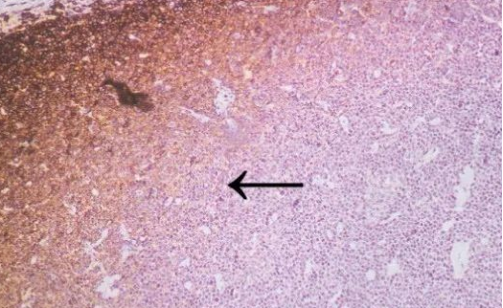

CD45 staining of paraffin-embedded human lymph node sections: Due to insufficient tissue fixation, lymphocytes at the edge of the lymph node show strong CD45 positivity, while those in the inner part of the tissue exhibit weak positivity, leading to uneven staining overall.

2 HE staining of paraffin-embedded renal tissue sections: Delayed or incomplete fixation results in blurred cell nuclei and poor contrast.